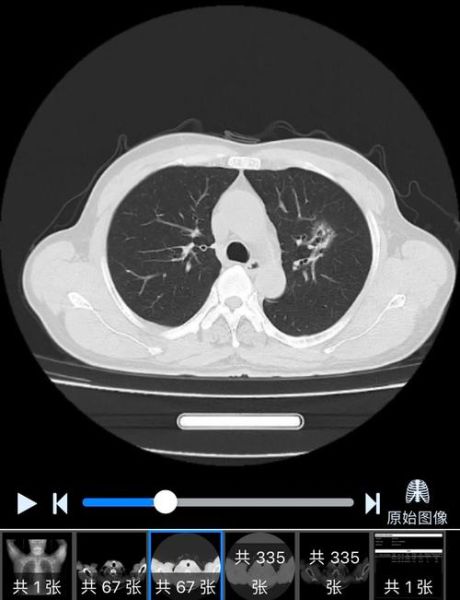

很多人拿到体检报告,看到“肺部CT”四个字就开始紧张: **“这张黑底灰影的片子到底怎么看?”** **“医生说的结节、条索、磨玻璃到底长什么样?”** 肺图片大全的价值就在于,把抽象的文字描述变成直观的视觉对照,让普通人也能秒懂自己的片子。 ---一张标准肺部CT包含哪些视角?

1. **肺窗**:专门看肺泡、支气管,呈灰黑色,像冬天结霜的玻璃。 2. **纵隔窗**:重点观察心脏、大血管,呈灰白色,像大理石纹理。 3. **骨窗**:锁定肋骨、胸椎,呈亮白色,像X光片的加强版。 把三种窗口连起来看,才能避免漏诊。 ---肺部CT常见“异常信号”长什么样?